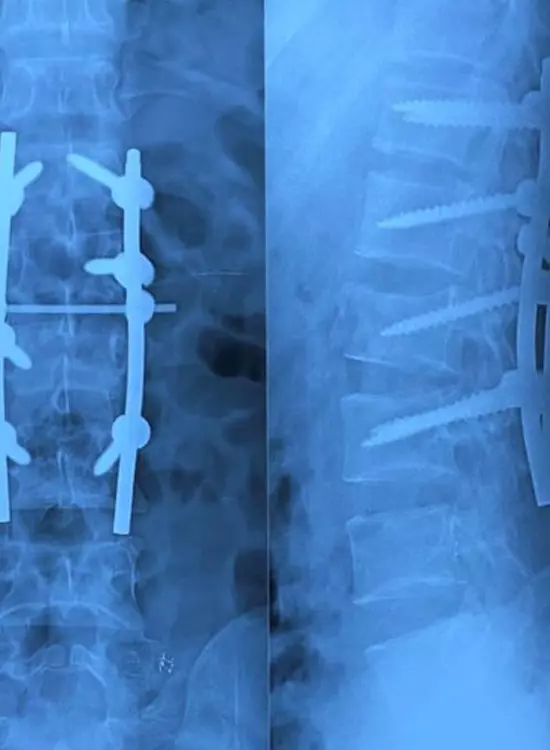

Cirugía de Columna

Galería

Galería y Medios